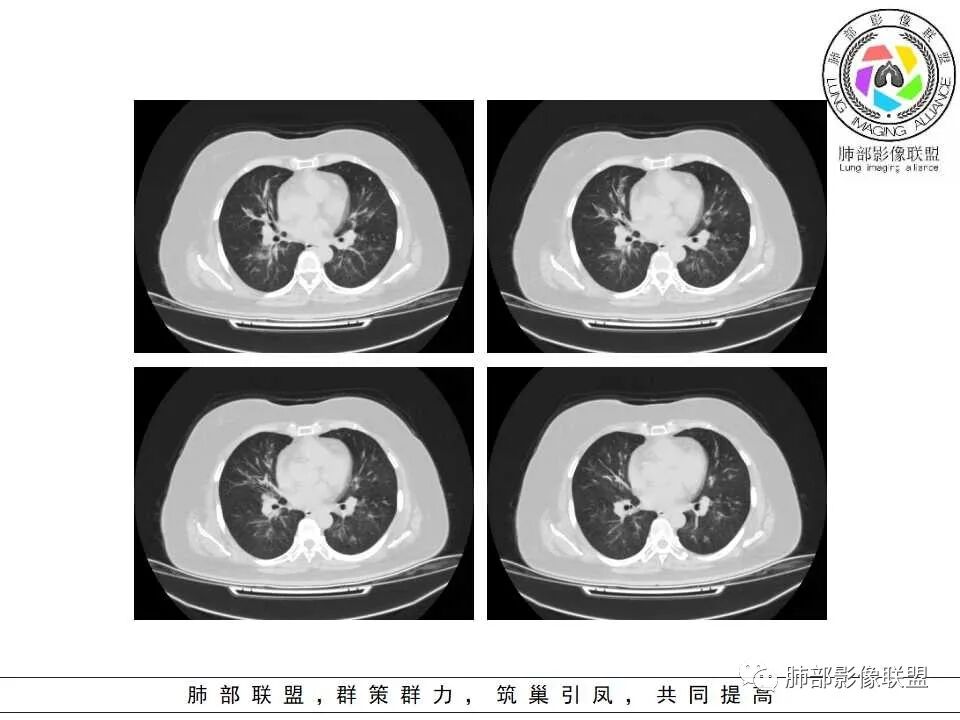

老年女性,发现白细胞升高两年,此次入院多次查外周血白细胞>30*10^9/L,淋巴降低,CRP显著升高,但病程中无发热,以细菌性炎不好解释;CT提示有脾大,结合外周血象,首先考虑存在血液系统疾病(白血病)基础,且未系统诊治;肺部CT提示双肺中轴间质增粗,伴随支气管管壁增厚?多发树丫及腺泡结节,部分呈点晕征,可见肺动脉分枝增粗,一元论考虑白血病肺部浸润;二院论考虑白血病并发气道侵袭曲霉。以患者病程进展看,更倾向于白血病肺部浸润。

肺动脉增粗,支气管有改变

左侧腔内有粘液栓,右侧支气管局部有扩张

支持气道病变,弥漫,支气管壁增厚,糖尿病,支持霉菌

肺动脉高压:性质待查,血象哪位老师解释一下,看右上支气管,怀疑以前都有过

1.病灶沿支气管分布的特点相当明显,相应支气管壁广泛增厚。这种与支气管关系极为密切的片影和/或结节影,常高度提示气道相关感染,如支气管肺炎。

2.患者两肺多发病变,具有广泛性。如此广泛分布更多见于免疫低下的机会性感染。

3.支气管壁广泛增厚对气道侵袭性曲霉病具有一定的提示意义。注意患者没有支气管扩张,临床也未提供IGE等实验室资料。

1.器官支气管管套样壁增厚和/或支气管扩张,注意壁增厚较均匀,和/或伴有播散性小片影及结节影,注意这些小片影或结节影边界有时较普通炎性病灶清楚。

2.可以阻塞支气管造成肺不张而酷似中央型肺癌。偶而可呈大范围毛玻璃样影。